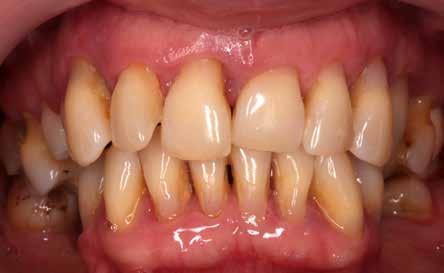

Az 50 éves nőpáciens az alsó és felső állcsont területén egyaránt panaszt (fájdalom, ráharapási érzékenység) okozó, harmadfokban mozgatható fogak miatt jelentkezett rendelőnkben. Az általános anamnézisben említést érdemlő betegség, műtét nem szerepelt. Az elvégzett klinikai és radiológiai vizsgálatok (1–2. ábra) alapján fogai reménytelen parodontális státusúnak bizonyultak, hosszú távon sem megtartásuk, sem protetikai célú felhasználásuk nem volt lehetséges. A parodontális prognózis a fogak eltávolításának abszolút indikációját jelentette. Ezáltal mindkét állcsontban teljes foghiány kialakulásával kellett számolnunk. A protetikai szemléletű, „visszafelé” tervezés elveit követtük a hosszú távú funkcionális, esztétikai siker és szöveti stabilitás elérése érdekében: mindkét állcsontban overdenture típusú fogpótlás készítése mellett döntöttünk. A megfelelő implant-protetikai rehabilitáció alapja az implantátumok megfelelő pozicionálása. A korábbi parodontális kórfolyamat következtében a processus alveolarisokat érintő eredendő csontdeficittel kellett számolnunk, amelyet tovább súlyosbíthatott volna a hagyományos extrakciós technikát követő involúciós atrófia. Ezért a páciens kivizsgálása és megfelelő előkészítése után a fog eltávolításával egy időben PRF

27 VI. ÉVFOLYAM – 2023. 4. SZÁM

Sticky Tooth segítségével kivitelezett alveolus prezerváció mellett döntöttünk, a megfelelő csontos és mukogingivális gyógyulás minőségi és mennyiségi elősegítése érdekében. A PRF készítmény mennyiségét, minőségét, kezelhetőségét és hatékonyságát jelentősen befolyásolják a páciens laborértékei, ezért kezelési protokollunk szerint a műtétet megelőzően minden esetben laborvizsgálatot végzünk (hemoglobin: 134 g/liter, hematokrit: 0,43, fehérvérsejt: 6,6 G/liter, CRP: 13,60 mg/liter, vércukor: 6,2 mmol/liter, összkoleszterin: 7,00 mmol/liter, triglicerid: 1,08 mmol/liter, HDL koleszterin 2,57 mmol/liter, LDL koleszterin 1,12 mmol/liter), D3 vitamin: 117,5 nmol/liter).

A fogak eltávolítása és az alveoláris csont megőrzésének és regenerációjának segítése céljából elvégzett augmentáció altatásban történt. Óvatos, atraumatikus extrakciót követően eltávolítottuk a parodontális és periapikális gyulladásos folyamatok eredményeként jelen lévő sarjszövetet. A bukkális csontfal hiánya és a tervezett vertikális augmentáció miatt indokolt membrántechnika megfelelő kivitelezése céljából a felső állcsonton mukoperioszteális lebenyt képeztünk (3–4. ábra). Az alveolus prezervációt Sticky Tooth, PRF és titánerősítésű teflon (PTFE-Ti) membránok segítségével végeztük el, a J. Choukroun által megadott vérvételi és centrifugálási protokoll (28) elveinek betartásával: kizárólag Process for PRF Duo Quattro System eszközöket, centrifugát, vérvételi egységet és csöveket, a membránok előállításához PRF Boxot használtunk. Az A-PRF és S-PRF csöveket a PomPac eljárásnak megfelelően 4 Celsius-fokra előhűtöttük. Az eltávolított fogak makroszkópos tisztítását és darabolását nagy fordulattal (300 000 RPM) fogászati turbinába helyezett gyémántfúróval végeztük, majd Tooth Transformer™ berendezéssel, annak gyári reagens rendszerével kezelt őrleményt nyertünk. A Sticky Tooth készítmény előállítása a PRF készítmény és az őrlemény

A fogak eltávolításának indikációja

A bukkális csontállomány teljes felszívódását és a fogak jelentős mobilitását okozó előrehaladott parodontális folyamat, a fogak eltávolításának abszolút indikációját jelenti. Tapasztalataink szerint ilyen esetben a fogak megtartását célzó regeneratív kezelésektől hosszú távú siker nem várható, az adekvát oki terápia a fog eltávolítása.